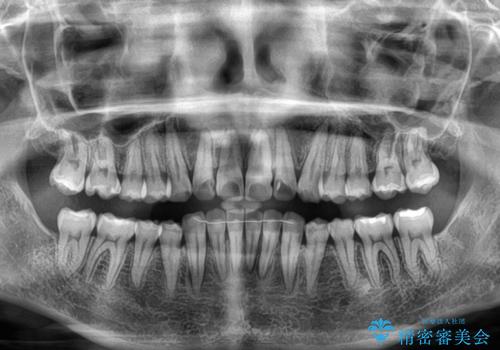

前歯の捻れを改善するとともに、口元が少しでも引っ込むように治療計画を立て、仕上げることができました。

長時間の装着を徹底し、遠方からの通院にもかかわらずしっかりと通院いただき、予想よりも早く治療を終えることができました。